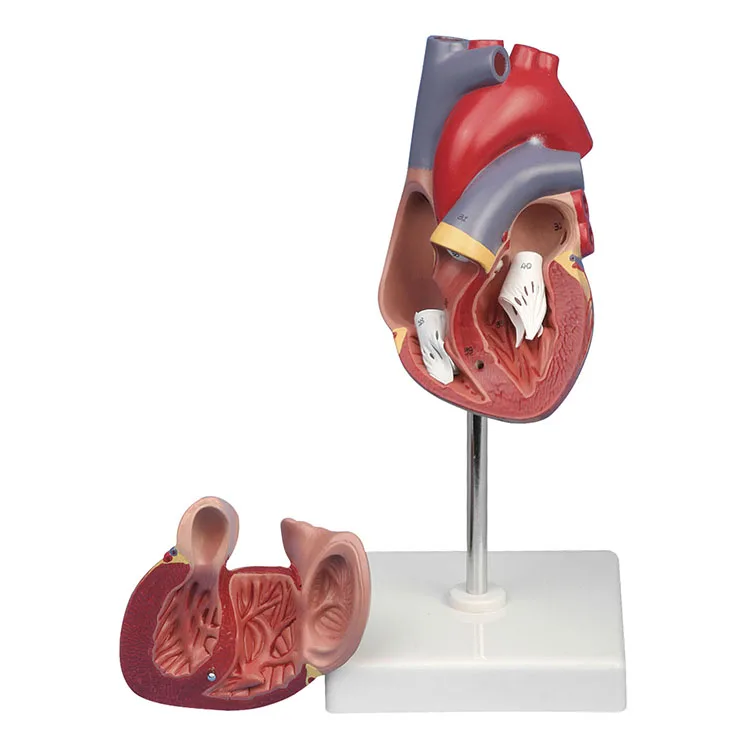

ขยายกายวิภาคหัวใจมนุษย์รุ่น 3 ชิ้นส่วน – Buy กายวิภาคหัวใจ,หัวใจ … หัวใจมนุษย์ การออกแบบรายละเอียด ภาพประกอบสต็อก – ดาวน์โหลดรูปภาพตอนนี้ …

ชีวิตพลาสติกกายวิภาคหัวใจมนุษย์รุ่น2ชิ้นส่วน – Buy การสอนรุ่น,Anatomy … ช็อคโกแลตรูปหัวใจ [ภาพวาดฟรี] | OkusanPix

ชีวิตพลาสติกกายวิภาคหัวใจมนุษย์รุ่น2ชิ้นส่วน – Buy การสอนรุ่น,Anatomy … ขนมช็อกโกแลตแท่ง ตรา โชกี้ โชกี้ 1 บาท แพ็ค 100 ชิ้น | Shopee Thailand

ขนมช็อกโกแลตแท่ง ตรา โชกี้ โชกี้ 1 บาท แพ็ค 100 ชิ้น | Shopee Thailand ชีวิตพลาสติกกายวิภาคหัวใจมนุษย์รุ่น2ชิ้นส่วน – Buy การสอนรุ่น,Anatomy …

ชีวิตพลาสติกกายวิภาคหัวใจมนุษย์รุ่น2ชิ้นส่วน – Buy การสอนรุ่น,Anatomy … รักสุดใจ! ช่อช็อกโกแลตให้เธอ รวมไอเดียช่อช็อกโกแลตสื่อรัก มอบให้แฟน

In-306 3d กายวิภาคศาสตร์หัวใจมนุษย์รูปแบบทางการแพทย์พลาสติกกายวิภาค … หัวใจมนุษย์ ภาพสต็อก – ดาวน์โหลดรูปภาพตอนนี้ – หัวใจ – อวัยวะภายใน, การ …

หัวใจวิทยาศาสตร์เรื่องกายวิภาคศาสตร์ทางการแพทย์หัวใจมนุษย์รุ่นขาย – Buy … หัวใจวิทยาศาสตร์เรื่องกายวิภาคศาสตร์ทางการแพทย์หัวใจมนุษย์รุ่นขาย – Buy …

หัวใจวิทยาศาสตร์เรื่องกายวิภาคศาสตร์ทางการแพทย์หัวใจมนุษย์รุ่นขาย – Buy … Anatomy หัวใจมนุษย์รุ่นพลาสติกทางการแพทย์กายวิภาคหัวใจจัมโบ้รุ่นอวัยวะ …

Anatomy หัวใจมนุษย์รุ่นพลาสติกทางการแพทย์กายวิภาคหัวใจจัมโบ้รุ่นอวัยวะ … รูปช็อกโกแลตหัวใจพร้อมน้ำเชื่อม PNG , วาเลนไทน์วัน, หัวใจ, วันแห่งความ …

3d Anatomy หัวใจมนุษย์รุ่นพลาสติกทางการแพทย์กายวิภาคหัวใจจัมโบ้รุ่น … หัวใจวิทยาศาสตร์เรื่องกายวิภาคศาสตร์ทางการแพทย์หัวใจมนุษย์รุ่นขาย – Buy …

หัวใจวิทยาศาสตร์เรื่องกายวิภาคศาสตร์ทางการแพทย์หัวใจมนุษย์รุ่นขาย – Buy … ส่งไว🚀24ชม. เจบีช็อกโกแลต รูปฟุตบอล เหรียญทอง เหรียญเงิน ทองแท่ง หัวใจ …

Anatomy หัวใจมนุษย์รุ่นพลาสติกทางการแพทย์กายวิภาคหัวใจจัมโบ้รุ่นอวัยวะ … ภาพประกอบแบนเวกเตอร์หัวใจมนุษย์ขนาดใหญ่บนพื้นหลังสีขาว ภาพประกอบสต็อก …

หัวใจมนุษย์กายวิภาครุ่นวิทยาศาสตร์การแพทย์รูปแบบการสอน ห้องหัวใจมนุษย์: คำอธิบายโครงสร้างหน้าที่และประเภท

หุ่นจำลองหัวใจมนุษย์ 3d มนุษย์กายวิภาครุ่นหัวใจมนุษย์สำหรับซัพพลายเออร์แบบครบวงจรวิทยาศาสตร์ …

3d มนุษย์กายวิภาครุ่นหัวใจมนุษย์สำหรับซัพพลายเออร์แบบครบวงจรวิทยาศาสตร์ … 3d Anatomy หัวใจมนุษย์รุ่นพลาสติกทางการแพทย์กายวิภาคหัวใจจัมโบ้รุ่น …

3d Anatomy หัวใจมนุษย์รุ่นพลาสติกทางการแพทย์กายวิภาคหัวใจจัมโบ้รุ่น … อวัยวะหัวใจของมนุษย์ | องค์ประกอบกราฟฟิก แบบ PSD ดาวน์โหลดฟรี – Pikbest

หัวใจมนุษย์กายวิภาครุ่นวิทยาศาสตร์การแพทย์รูปแบบการสอน 15 Porch ช็อกโกแลต Fudge แม่พิมพ์ซิลิโคนหัวใจรูปเค้กช็อกโกแลตตกแต่ง DIY …

อุปกรณ์การศึกษากายวิภาคศาสตร์รุ่นหัวใจมนุษย์รุ่นสำหรับโรงเรียนขนาดชีวิต … วิธีทำ “นามะช็อกโกแลต” ของฝากยอดฮิตจากญี่ปุ่น อร่อยหรูดูแพง แต่ทำง่าย …

In-306 3d กายวิภาคศาสตร์หัวใจมนุษย์รูปแบบทางการแพทย์พลาสติกกายวิภาค … บอลลูนหัวใจมนุษย์ Angioplasty เวกเตอร์ ภาพประกอบ ภาพประกอบสต็อก – ดาวน์ …

โรงงานโดยตรงขาย Anatomy หัวใจมนุษย์การฝึกอบรมชุดอวัยวะภายในรุ่น – Buy …